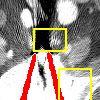

Sinogram data is inherently periodic along the projection direction, while DuDoNet uses zero padding for convolutions in SE-Net which ignores the periodic information. Here, to offer more useful information for convolution, we propose a new padding strategy for sinogram data using periodic padding along the direction of projection angles and zero padding along the direction of detectors, as shown in Fig. 6.

Effect of sinogram padding (SE-Net vs SEp-Net). Sinogram padding mainly improves the performance in the group with the largest metal objects, with a PSNR gain of 0.15 dB and an MSE reduction of 0.00048. As shown in Fig. 4, the model with sinogram padding restores finer details of soft tissue between large metallic objects because more correct information is retained by periodic padding than zero-padding.